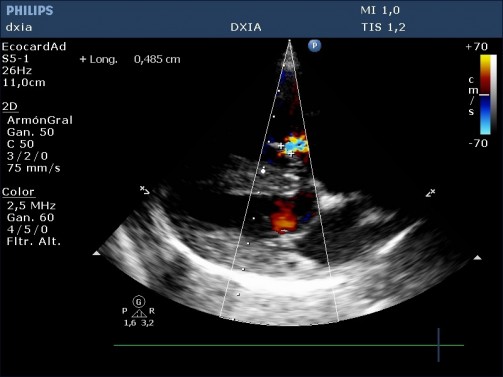

Leve engrosamiento de cúspides de la VT

Insuficiencia tricuspídea excéntrica de alta velocidad (4,2 m/seg)

Arteria pulmonar dilatada pero perfil flujo pulmonar debido a:

- Conducto arterioso persistente, aunque no se visualiza, no puede descartarse completamente. Habría que realizar una prueba de contraste.

- Hipertensión primaria congénita por retención de características fetales en la circulación pulmonar.